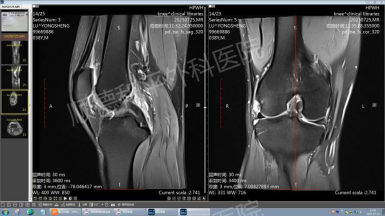

•卢先生,38岁,右膝痛风急性发作,站立困难。关节镜下结晶清除仅用50分钟,术后当天疼痛评分由9分降至2分。